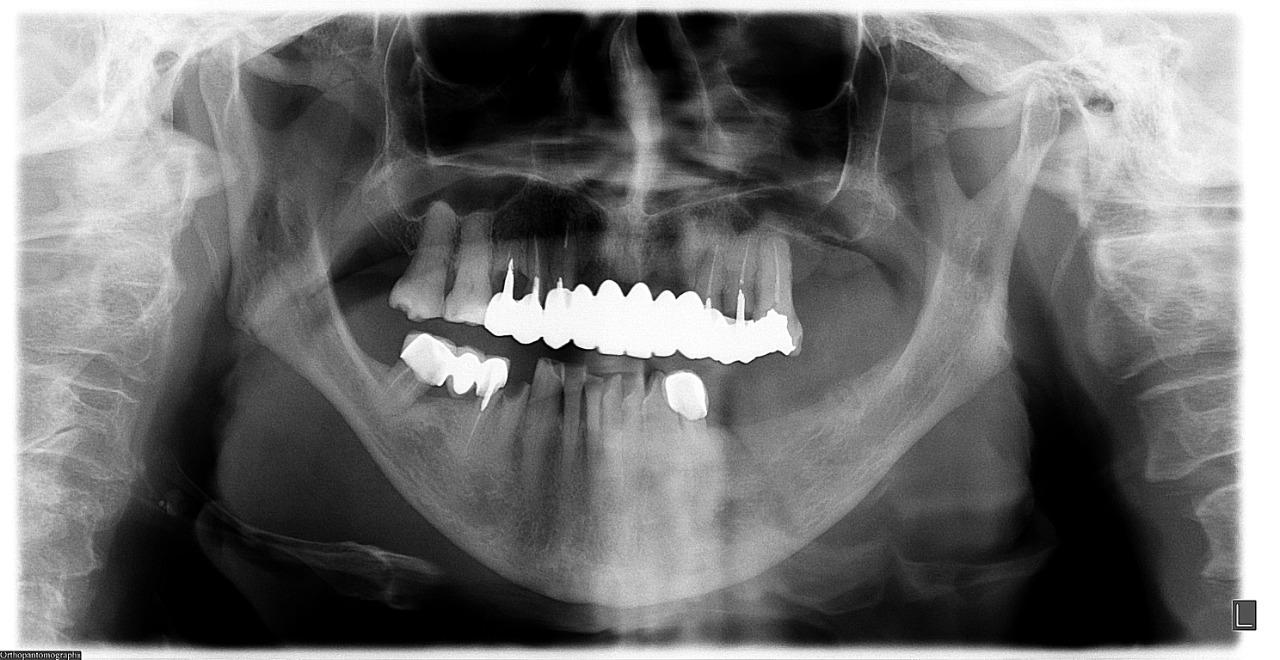

Prótesis híbrida

Son prótesis sin paladar que va fija a unos implantes, por lo tanto no es removible. Es el tratamiento perfecto para pacientes que están cansados de tener prótesis totales, donde no pueden tener buena masticación y degustación de los alimentos.